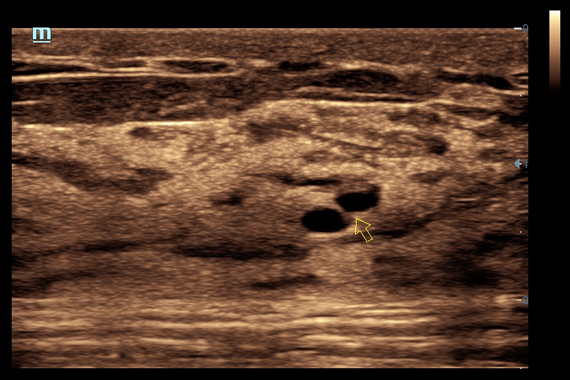

• iNeedle™ - улучшенная визуализация игл при проведении биопсии линейными датчиками

• Natural Touch Elastography - опция оценки эластичности ткани (эластография), с программой анализа. Действует на линейных датчиках 7L4A, L14-6NE и L9-3E

• Small parts package - предустановленные параметры, аннотации, маркеры, программы измерений для исследования малых (поверхностных) органов